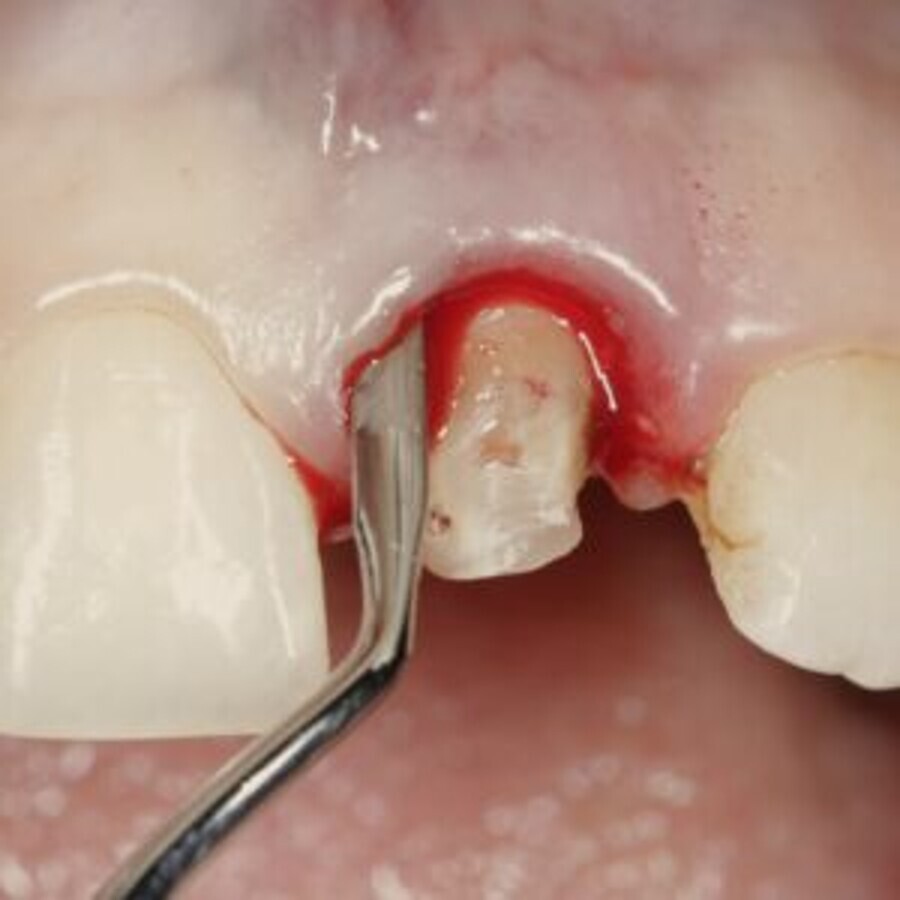

Fig 1: Pouch preparation in the central incisor region